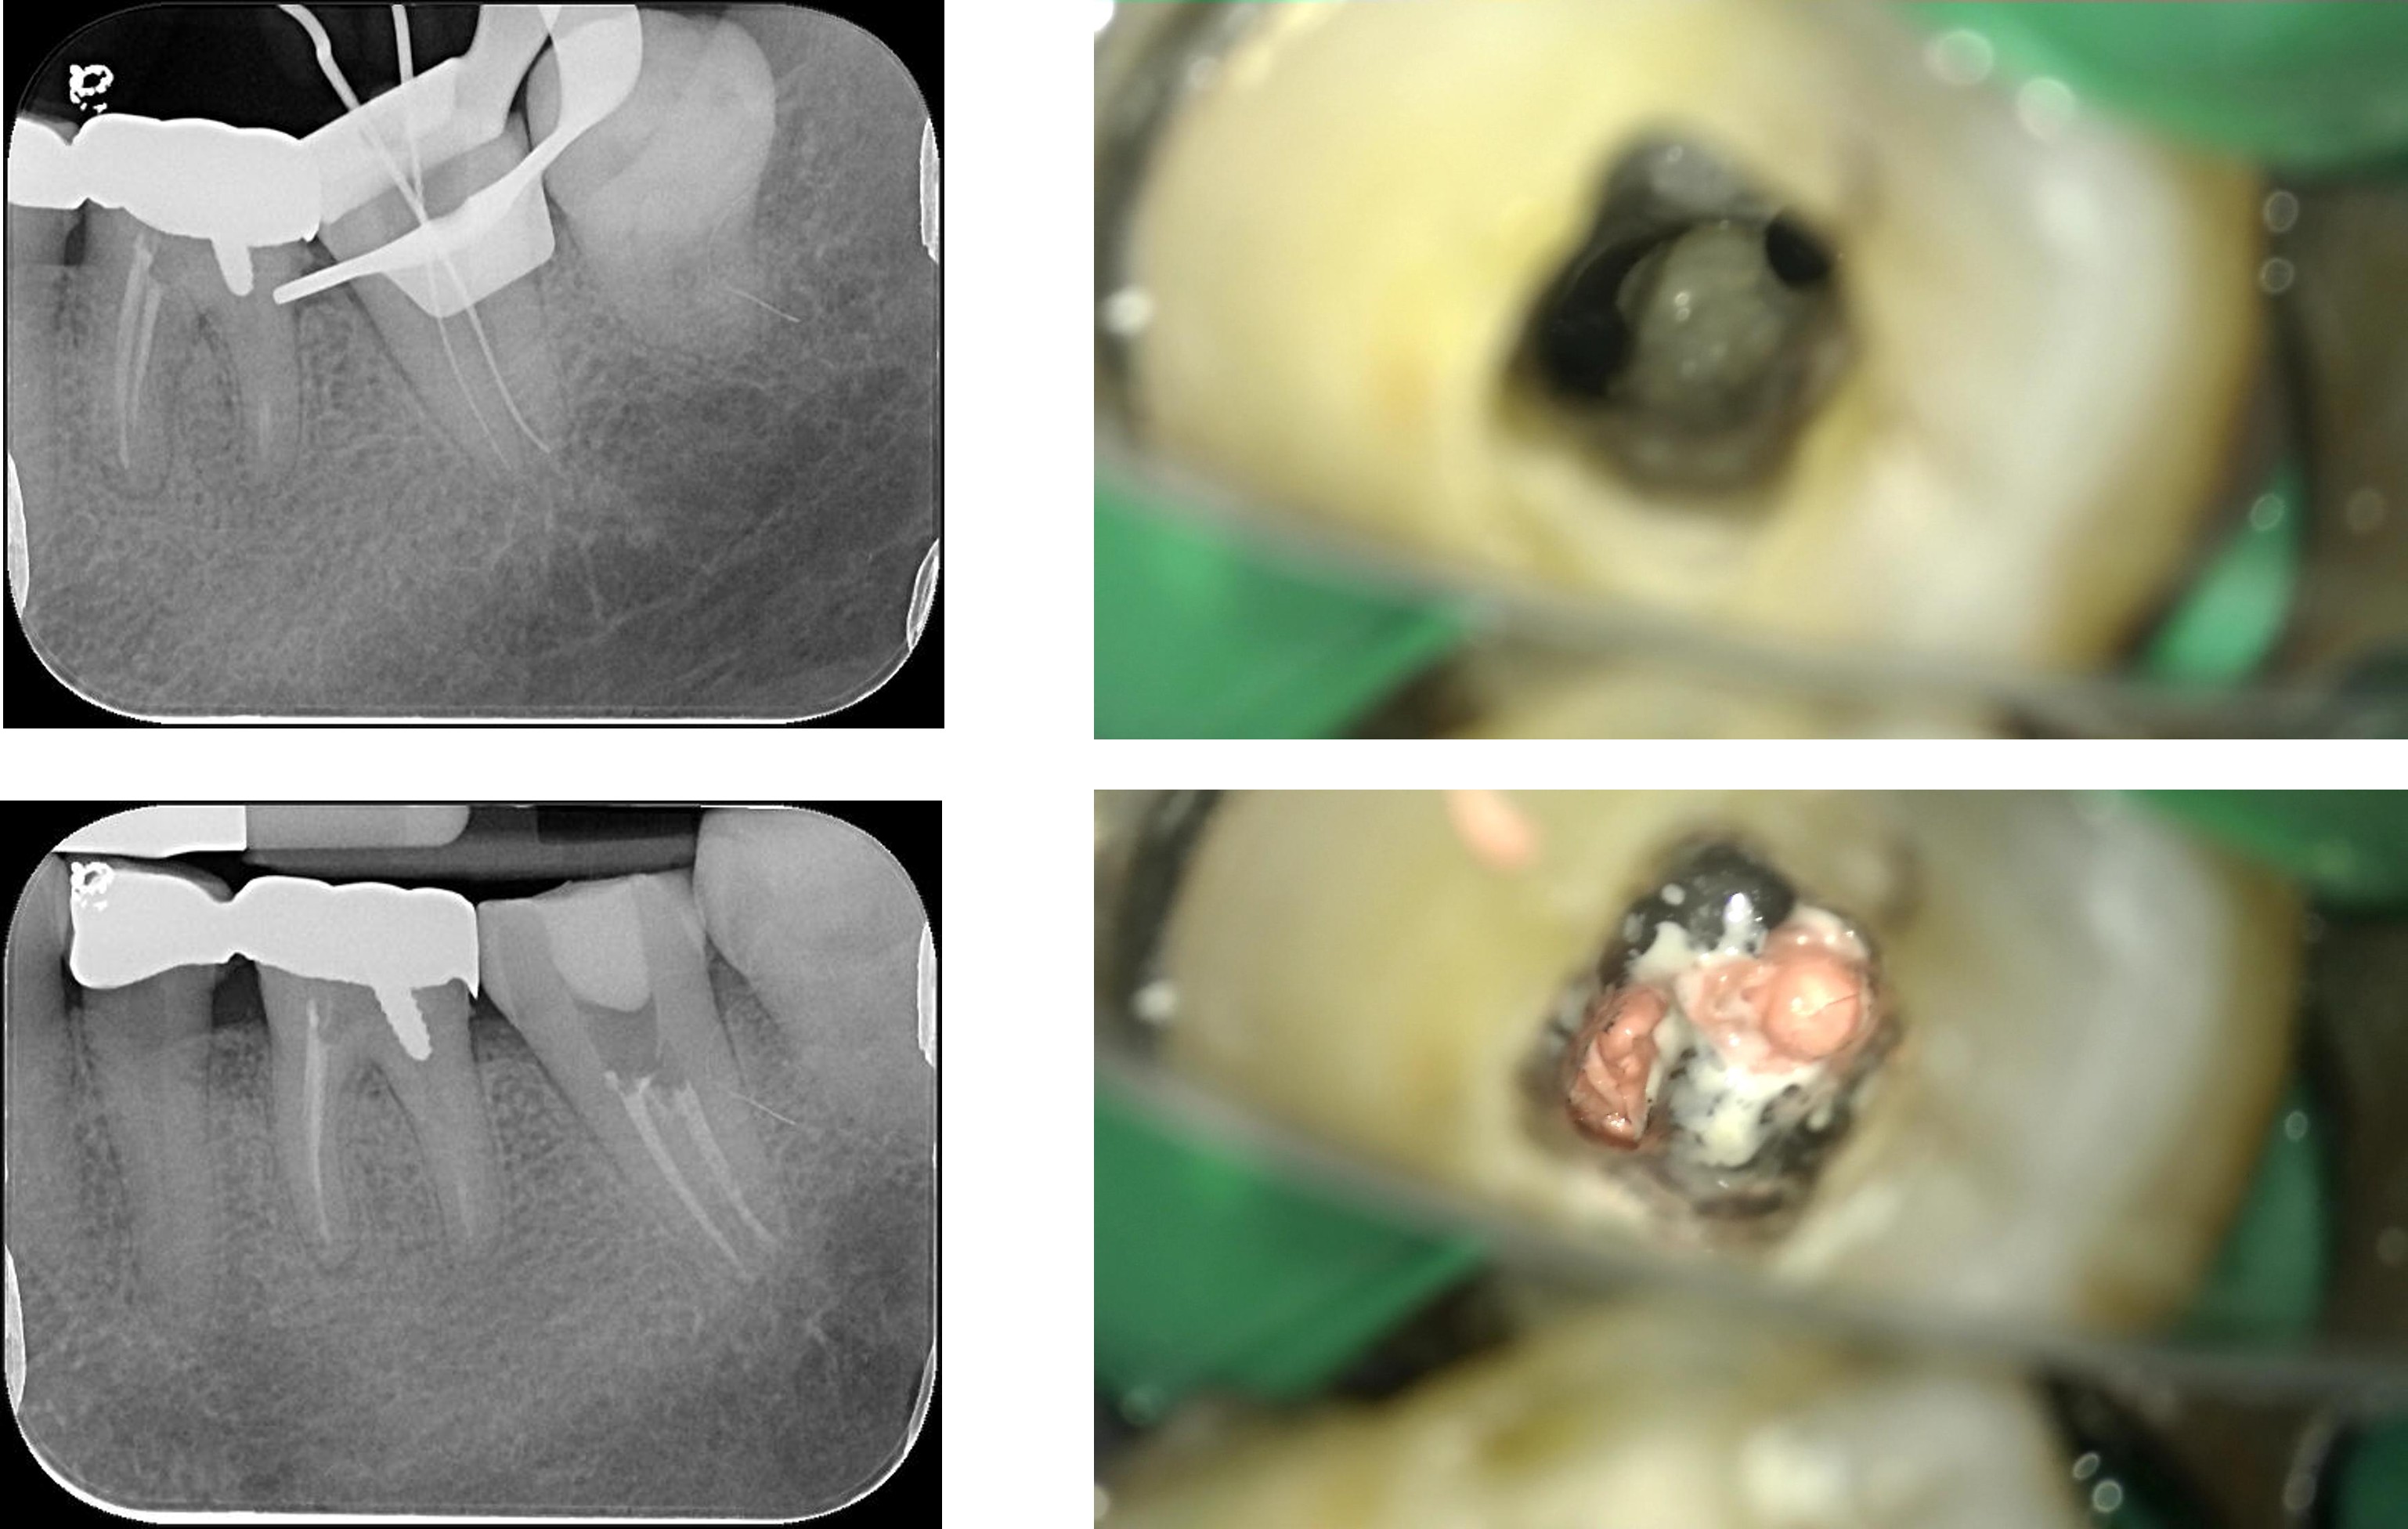

膺復前評估牙齦、牙齒狀態

照相比色